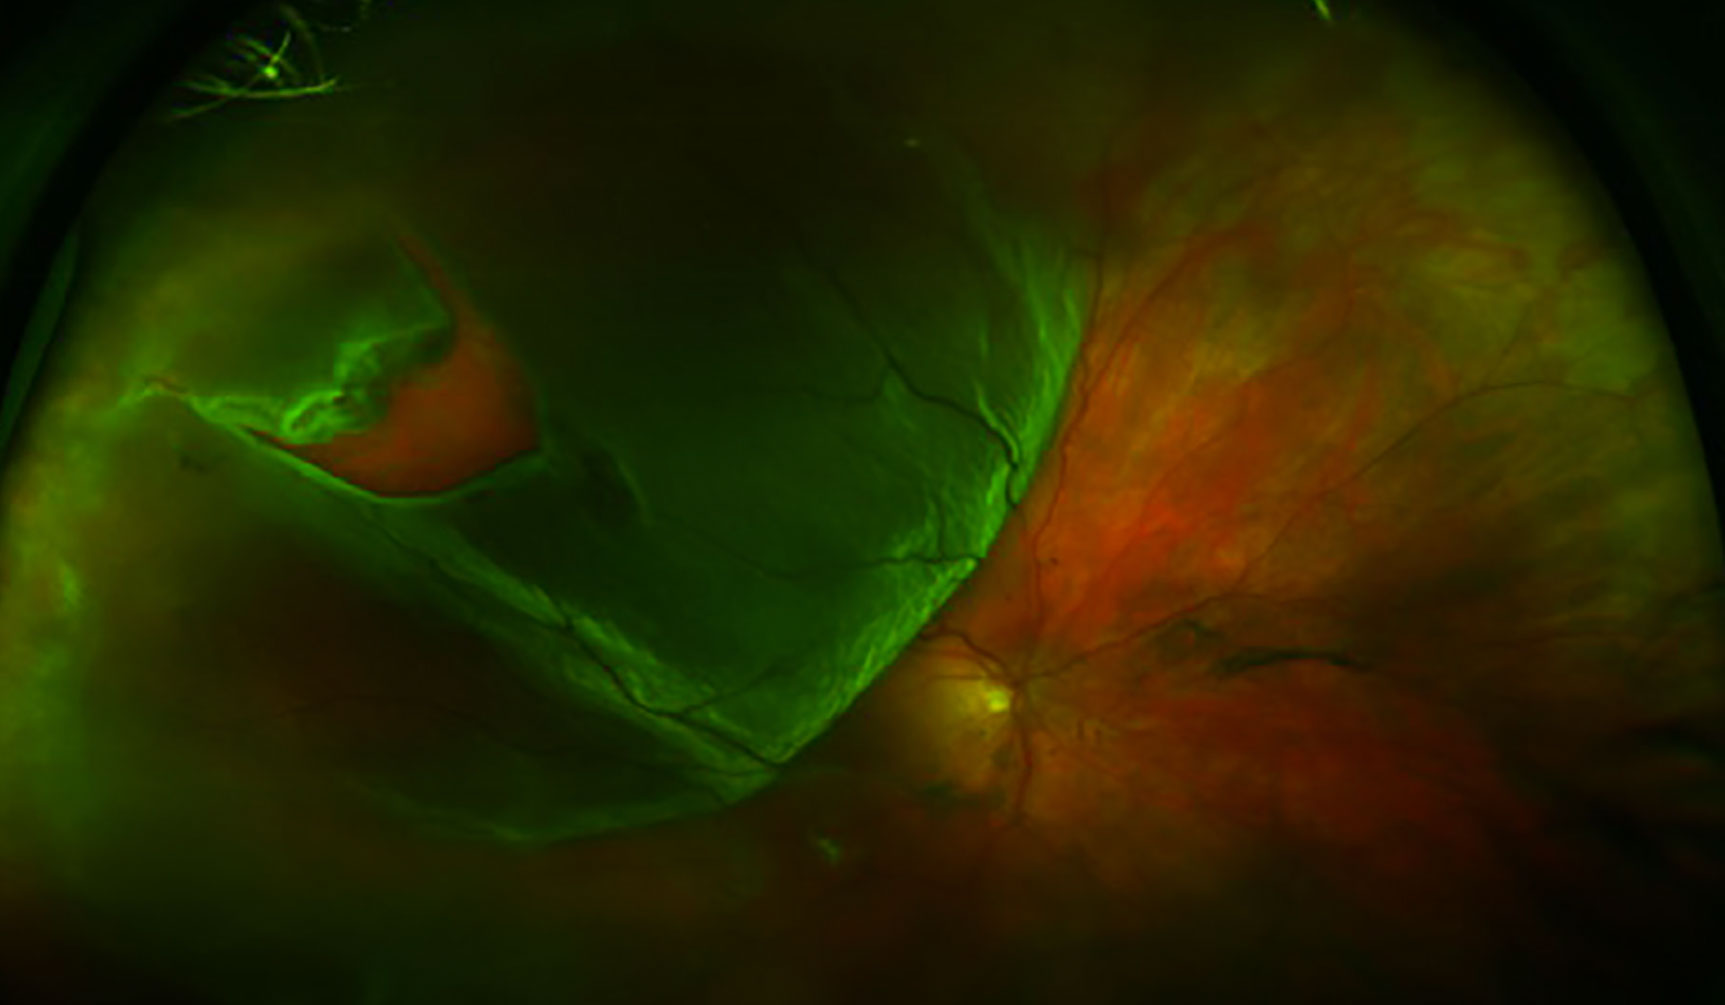

열공망막박리(RRD)는 **망막열공(retinal break)**을 통해 유리체액이 망막하 공간으로 유입되어 신경감각망막이 RPE에서 분리되는 안과 응급질환입니다. 치료하지 않으면 실명에 이릅니다.

분류 및 증상/징후 (Classification & Signs)

증상

- 비문증 → 광시증 → 시야결손(커튼 치는 듯) → 중심시력 저하(macula off)

분류

- Macula-on: 중심와 비침범 — 24-48시간 내 수술 권고

- Macula-off: 중심와 침범 — 가능한 빨리 (시력 예후 제한적)

- 산동 안저검사: 주변부까지 scleral depression — 열공 위치/수, 박리 범위